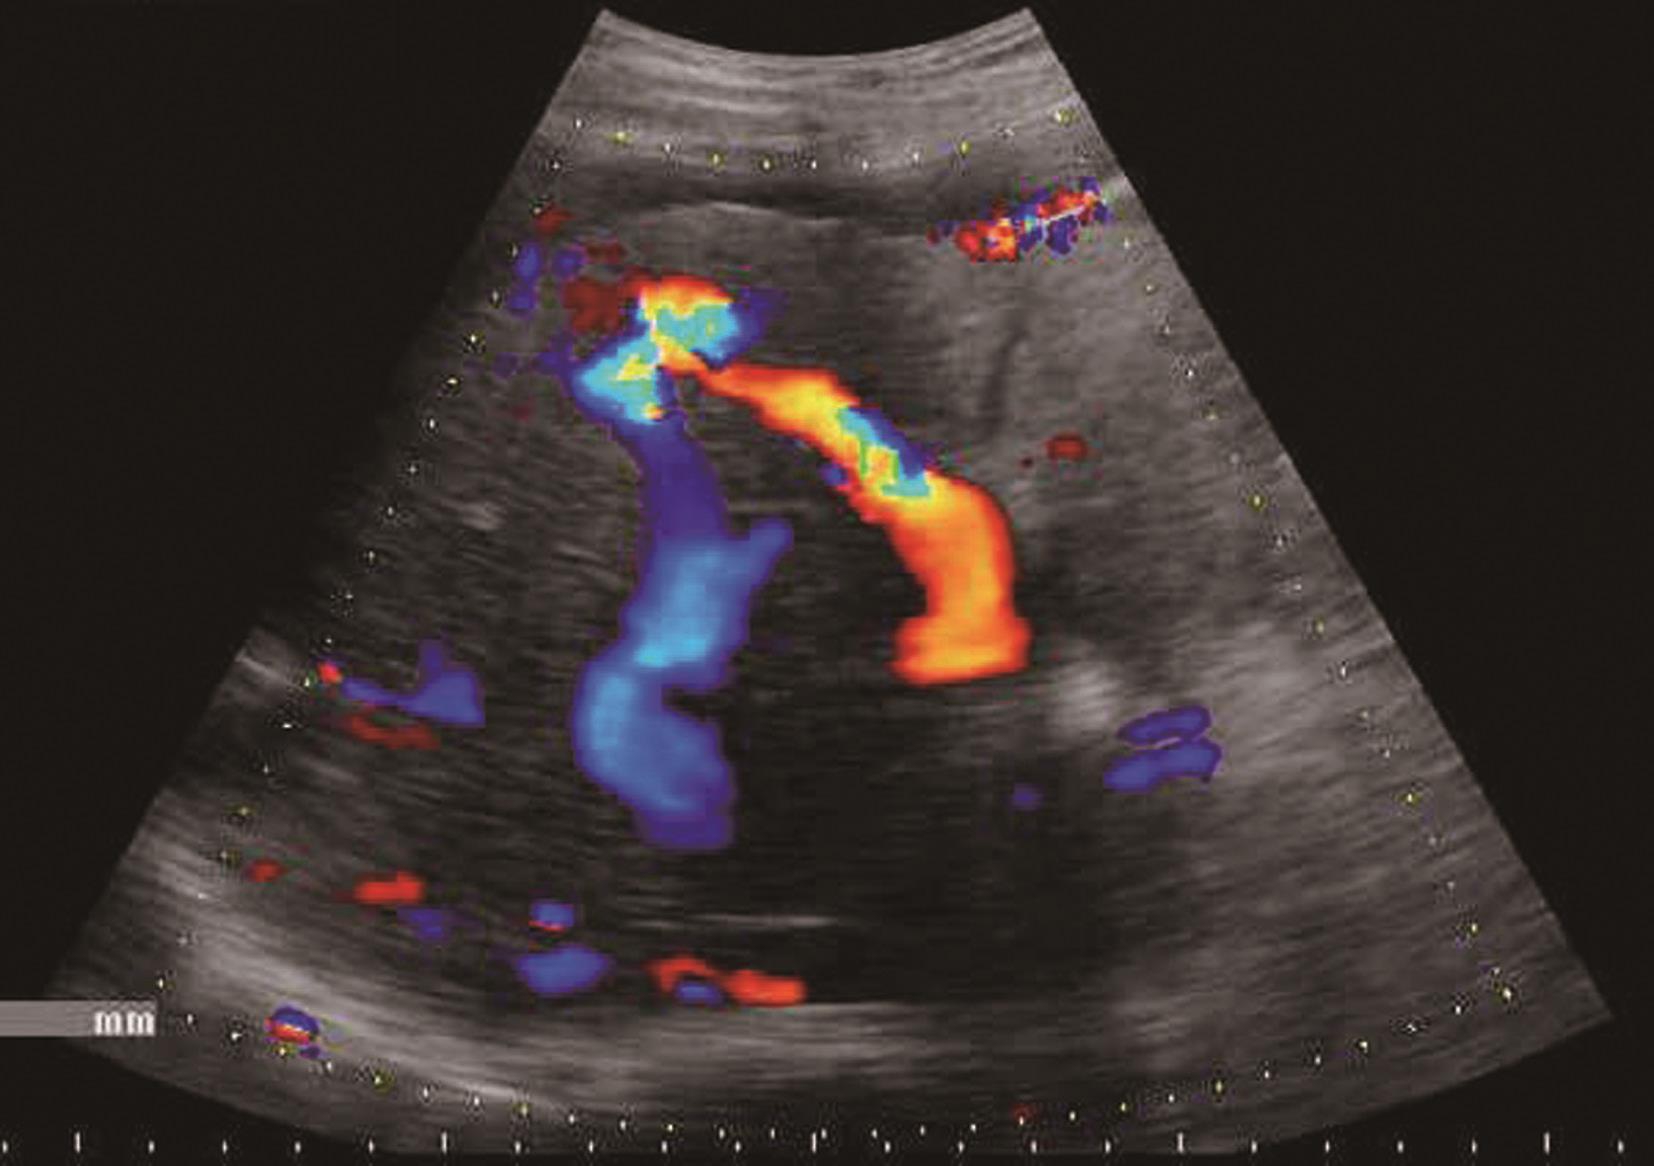

(3)肝血管:

肝内血管网变少。①门静脉高压:门静脉系统血管粗细与门静脉压力呈正相关。门静脉主干内径≥1.4cm,彩色多普勒显示门静脉色彩暗淡,严重者门静脉内显示双向血流或离肝血流,频谱多普勒超声检测正常的轻度波动消失,血流频谱低平或双向、反向血流,峰值流速一般低于20cm/s,同时脾静脉(内径≥0.8cm)及肠系膜上静脉增宽(内径≥0.7cm),有时可见呈瘤样扩张或脾肾静脉分流,部分患者可见门脉血栓形成及海绵样变性。②肝静脉可受挤压变细或粗细不均,血流频谱。部分肝静脉变细,纹理紊乱,仅见粗细不均、迂曲的蓝色血流。多普勒频谱曲线S<D峰,或S、D峰相连呈驼峰。③肝内动脉:肝硬化后,由于门静脉循环障碍,可使肝动脉代偿性扩张和增生,并与门静脉吻合支沟通。结果使肝动脉血流量增加,二维灰阶显示肝动脉内径增宽,彩色多普勒超声显示肝门部与门静脉并行的搏动性血流信号,脉冲多普勒超声可测得较高的峰值血流速度。④侧支循环开放:脐静脉重新开放使圆韧带内已闭塞的脐静脉分离而出现管状无回声区,自门静脉左支囊部延向腹壁。彩色多普勒检查门静脉左支彩色条状管道沿圆韧带方向一直通向肝表面,并穿过肝包膜及肌层至腹壁。重新开放的脐静脉血流多少与门静脉高压的严重性呈正相关。⑤胃左静脉扩张:内径≥0.5cm,血流速度增快,血流方向向肝、离肝或双向。门静脉高压患者伴有胃左静脉扩张提示存在食管胃底静脉曲张。⑥脾大:多为中度或重度肿大。脾静脉在脾门部和脾实质内有扩张的征象,脾实质回声无明显变化或轻度增强。腹水:肝前、脾周围、肝肾间隙、腹侧、盆腔出现液性无回声区,形态不定,且随体位改变而有相应变化,最大径可超过10cm。肝硬化肝血管超声声像图表现如图5-21-5~图5-21-7所示。

图5-21-5 肝硬化门静脉扩张、腹水、门静脉-肝静脉瘘彩色多普勒图像